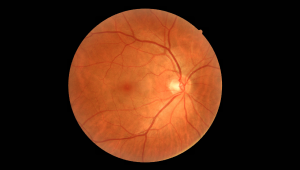

Високоякісне зображення сітківки

FundusVue создает высококачественные изображения сетчатки. Он предоставляет персоналу диагностики сетчатки глаза и системам искусственного интеллекта более точную и полезную информацию.